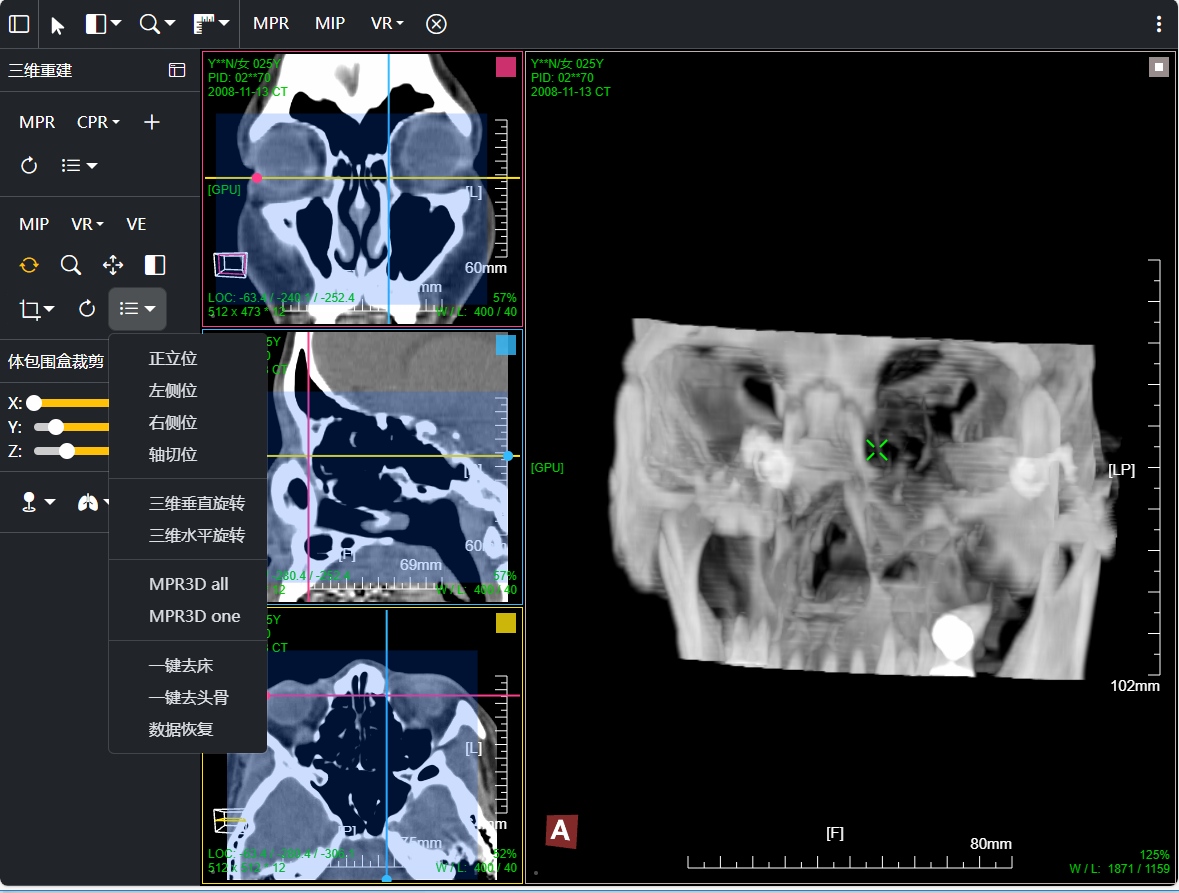

- 支持MPR、CPR、MIP、VR、VE三维图像处理;支持三维裁剪切割 / 一键去床

三维:MPR多平面重建(支持任意旋转)、CPR任意曲线切面重建、MIP最大密度、VR容积重建、VE虚拟内窥;任意三维裁剪、一键去床、一键去头骨、快速旋转、厚切MPR(最大密度/最小密度/均值/VR); 手工/半自动分割,分割目标三维渲染; 肋骨CPR拉伸渲染、牙神经管渲染、血管CPR拉直渲染等

八、三维浏览功能操作和截图

左键双击MPR窗口可在MPR三窗口和1x1窗口间切换;三维渲染窗口左键双击在在1x1视图模式和当前视图模式切换

点击MPR窗口右上角颜色块可AXIS轴位、CORO冠位、SAGI矢位切片切换

鼠标右键点击MPR窗口左下 切片位置指示器 可显隐十字交叉线; 左键点击MPR复位

鼠标左键点击MIP窗口左下 三维旋转状态指示器 可快速旋转到指定面; 右键点击三维旋转复位

厚切支持MIP最大密度 、MINIP最小密度、AVG均值密度、以及VR渲染

改变厚切层厚:1、预设层厚菜单(可配置) 2、拖动滑块快速改变 3、拖动十字交叉线上的层厚虚线

CPR曲面重建 、厚切曲面;

VR容积渲染;鼠标右键默认实时调整当前VR传输函数

支持VR传输函数预设配置; 支持用户自定义配置调整传输函数;

支持自由裁剪切割: 支持自由画笔 和 多边形轮廓选择裁剪区域模式

支持体包围盒裁剪: MPR蓝色mask区域位当前体包围盒设定有效区域

传输函数配置鼠标操作:滚动鼠标滚轮可改变当前X轴阈值范围

双击增加节点; 鼠标右键单击删除指定节点;左键可拖动节点或传输函数;

MIP 最大密度投影渲染: 鼠标右键默认实时调窗

鼠标滚轮改变切片位置

VR渲染一键去床体:为提高去床速度,可先进行体包围盒裁剪选择含有床体的部分然后点击一键去床功能

注: 部分检查床体可能不能完全去床干净,可继续通过手工自由裁剪的方式进行去除;

VR渲染一键去头骨:首先进行体包围盒裁剪选择头颅部分限制区域生长范围,然后点击一键去头骨功能

去除头骨后,取消体包围盒裁剪即可;其它操作同vr渲染操作,譬如右键微调VR传输函数,左键三维旋转等